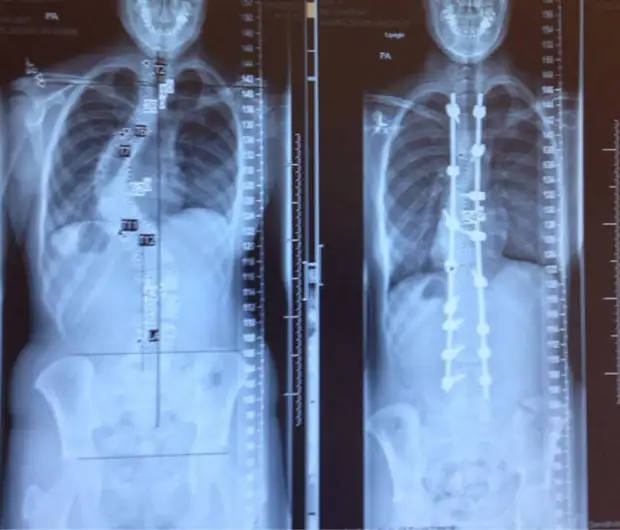

4. Позвоночник одного и того же человека до и после лечения сколиоза.